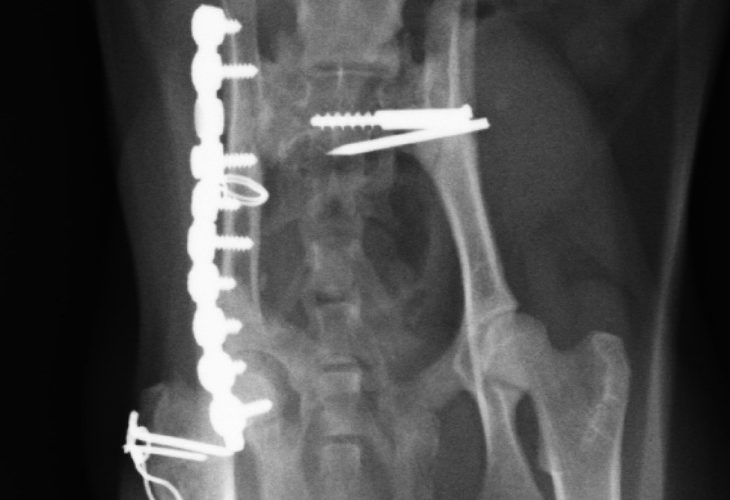

骨盤骨折